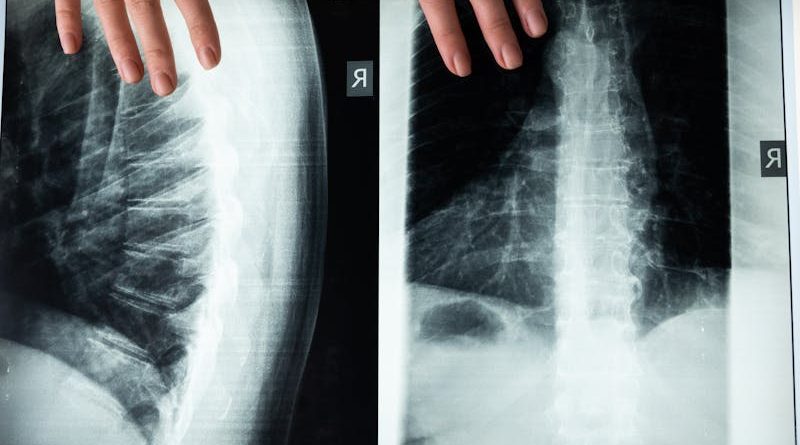

Acesta este probabil cel mai răspândit mit și totodată cel mai ușor de demontat. Doar o parte dintre investigațiile imagistice utilizează radiații ionizante. Radiografia convențională, tomografia computerizată și investigațiile de medicină nucleară fac uz de radiații X sau gamma. În schimb, ecografia se bazează pe ultrasunete, iar rezonanța magnetică folosește câmpuri magnetice puternice și unde radio. Niciuna dintre aceste din urmă două investigații nu expune pacientul la radiații ionizante, motiv pentru care se folosesc preferențial la copii, gravide și la pacienți care necesită monitorizări repetate.

Mai mult, chiar și investigațiile care folosesc radiații au evoluat semnificativ. Aparatele moderne de tomografie computerizată reduc doza de radiații cu 60-80% față de aparatele de acum două decenii, prin algoritmi avansați de reconstrucție și prin protocoale optimizate pentru fiecare tip de pacient și fiecare regiune anatomică. Beneficiul diagnostic depășește cu mult riscul minim asociat unei investigații justificate medical.

Această confuzie apare frecvent la pacienți, mai ales atunci când o ecografie inițială nu evidențiază nicio anomalie. Realitatea este că diferitele tipuri de imagistică oferă informații complementare, nu interschimbabile. Ecografia este excelentă pentru evaluarea organelor abdominale superficiale, a tiroidei și a sânilor la femeile tinere, dar are limite semnificative în vizualizarea structurilor profunde sau a celor înconjurate de aer și os.

RMN-ul, în schimb, oferă rezoluție anatomică superioară pentru țesuturile moi, vizualizează detalii imposibil de evidențiat ecografic și permite caracterizarea precisă a leziunilor descoperite. Cele două investigații nu se exclud reciproc, ci adesea se completează în arhitectura diagnostică modernă.